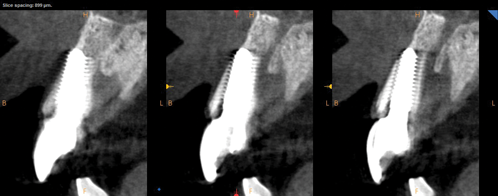

Fig 4. Preoperative CBCT cross-sectional view demonstrating very thin buccal cone.

Figure 4

Fig 8. CBCT at 1-year postoperative demonstrated the retention of the buccal portion of the root as well as maintenance of the buccal plate of bone. Beam hardening and volume averaging artifacts can be noted in the CBCT cross-section.

Figure 8